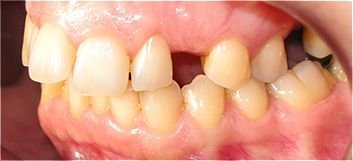

Apinhamento dentário severo e ausência do dente canino (dente 23).

![]() |

Após o tratamento ortodôntico e colocação de prótese fixa de cerâmica, para colocação do dente canino.